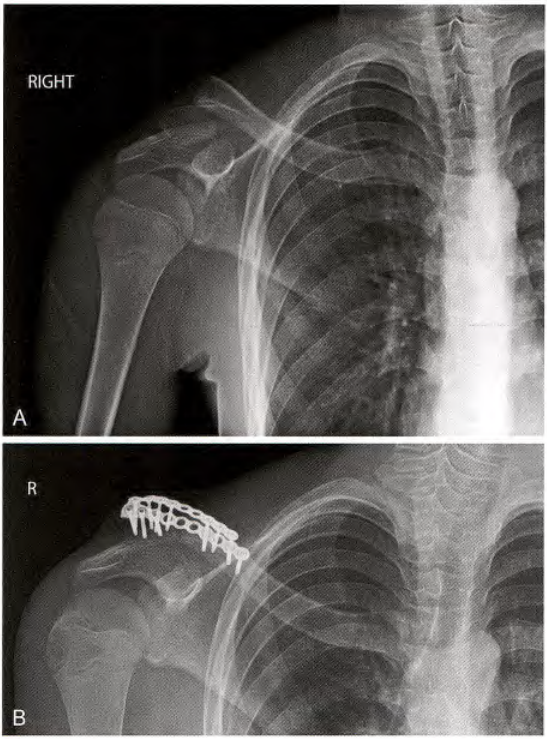

上方固定

对于上方固定,进行钢板塑形以适应锁骨上缘。从上向下依次固定螺钉,仔细检查,以避免损伤神经血管结构。

上部钢板固定